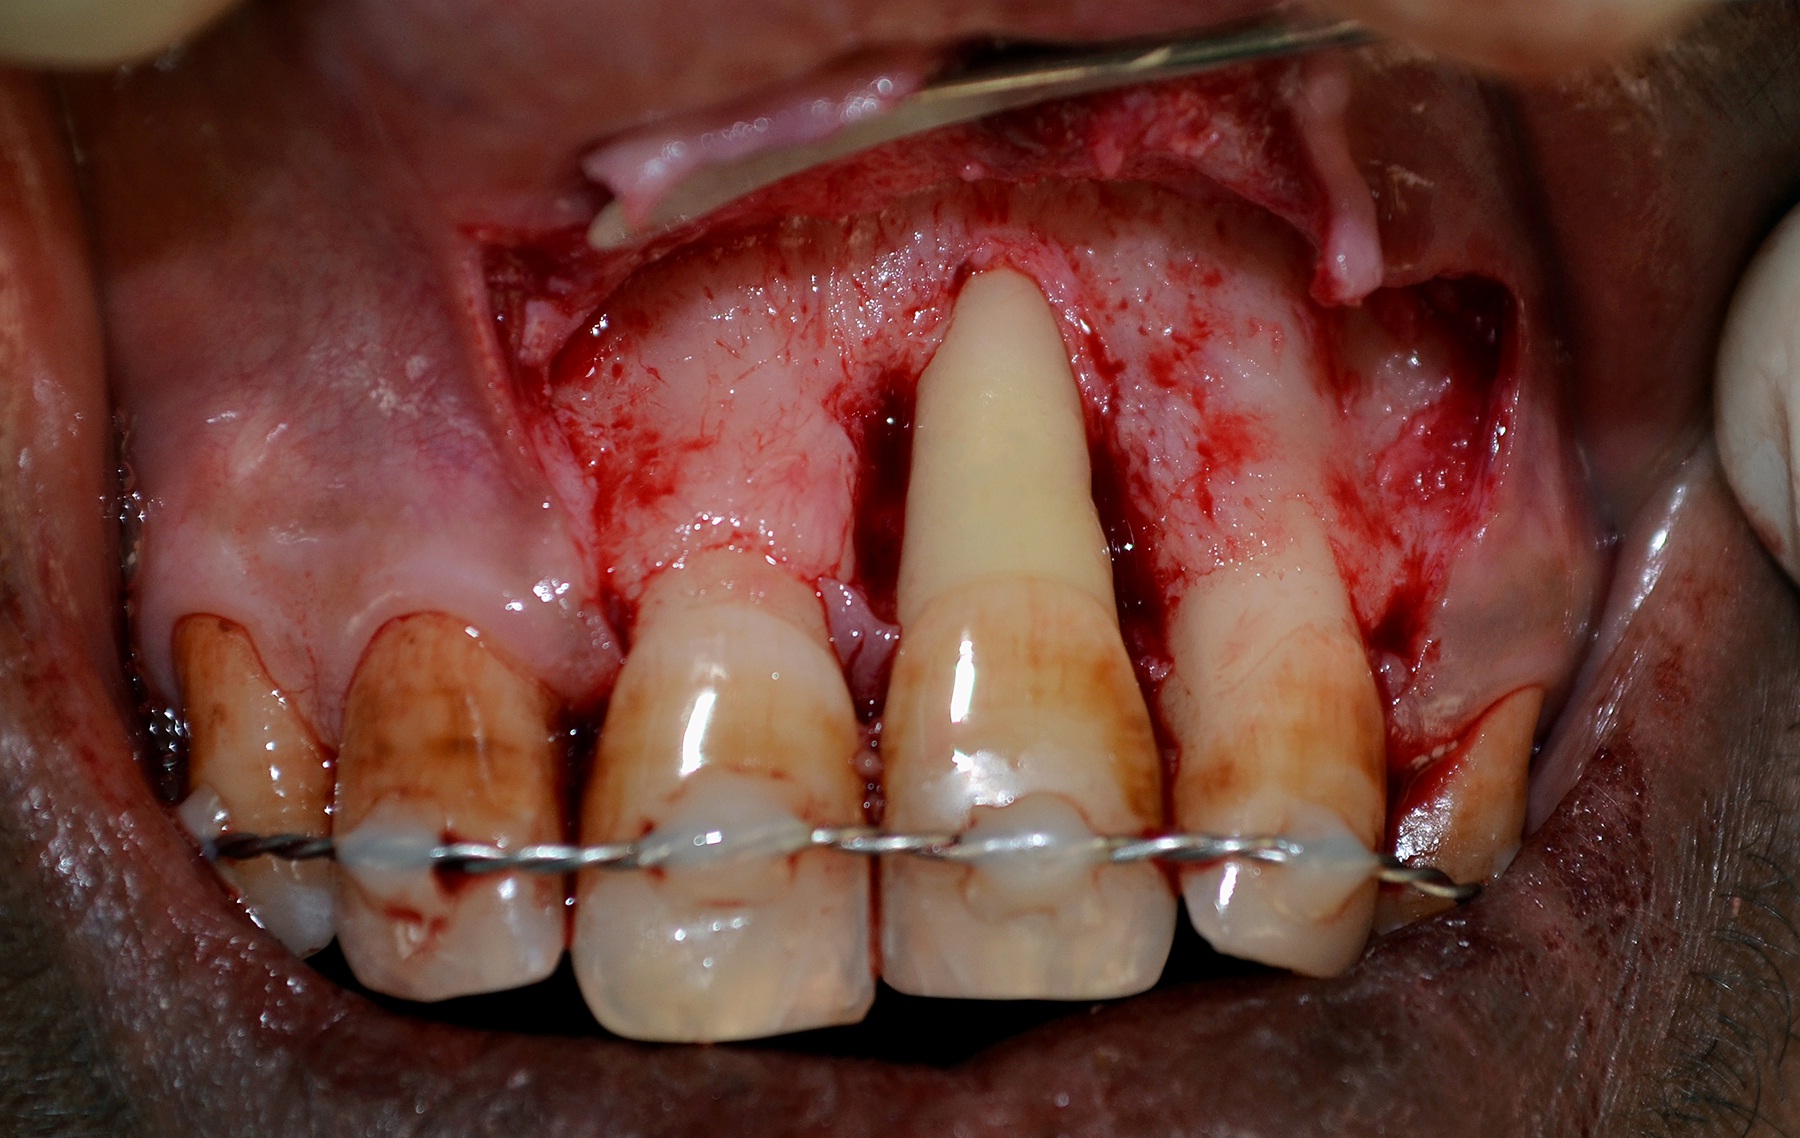

Replantation Procedure: After obtaining adequate anesthesia using Lignocaine hydrochloride 2%, a full thickness mucoperiosteal flap was reflected which revealed periodontal destruction extending beyond the root apex [Table/Fig-3]. Splint removal was followed by atraumatic tooth extraction. Extracted tooth was root planed with Gracey’s curettes for removal of calculus, remaining periodontal ligament and necrotic cementum and was immediately placed in a solution of tetracycline (500 mg of tetracycline dissolved in 20 ml saline) for 5 min.

Reflection of full thickness mucoperiosteal flap revealing bone loss beyond the apex of the root of left maxillary central incisor.